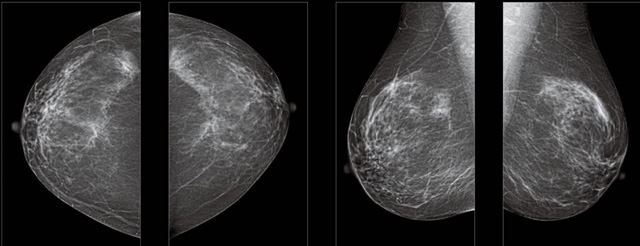

首先不同年龄阶段的乳腺筛查频次种类不一样。青春期女性第二性征明显发育开始,每个月进行自我乳腺检查。20-30岁的女性就不推荐进行乳腺检查,因为年轻女性的乳腺组织非常紧急。钼靶X光线等检查的射线不能辨别肿块跟腺体。身体就白吸收了辐射,影响了身体健康。每个月自检一次就是在洗澡时候,对着镜子看看乳房外观正常,皮肤溃烂、肿块、颜色改变、再摸一下有没小疙瘩。乳腺高危人群,特别是有乳腺CA遗传倾向的女性,乳腺导管跟小叶不典型增生,原位癌。30岁前有乳房放疗的女性。乳腺癌筛查可以把年龄提前到40岁前。40到70岁的女性可以在适合的机会筛查。

采用影像检查技术来发现疑似特定病检查跟人群的普查。一到两年进行一次X光线的乳腺检查。记过是C或者D型,可以加上B超协同?;箍梢砸荒暌淮魏舜殴舱馦RI检查。70岁以上的女性认为绝经的女性是比较安全的。实际上也有乳腺癌的风险。65岁以上风险也很大。也是需要进行机会性筛查。